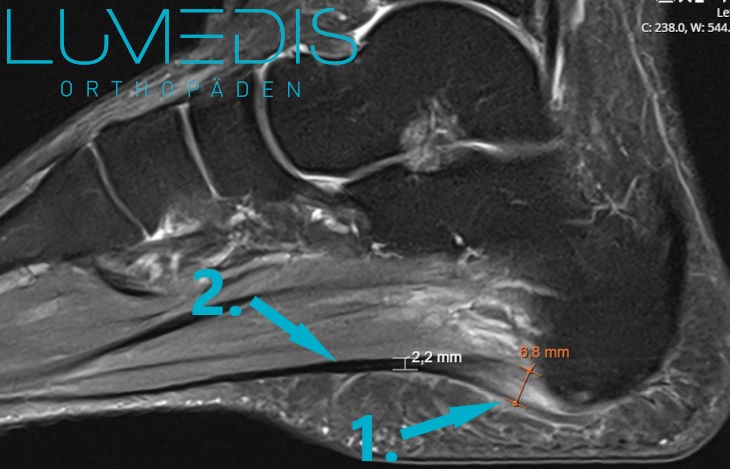

MRT einer schweren Plantarfasziitis

MRT einer Plantarfasziitis rechts

MRT vom Fuß (seitlicher Fuß T2)